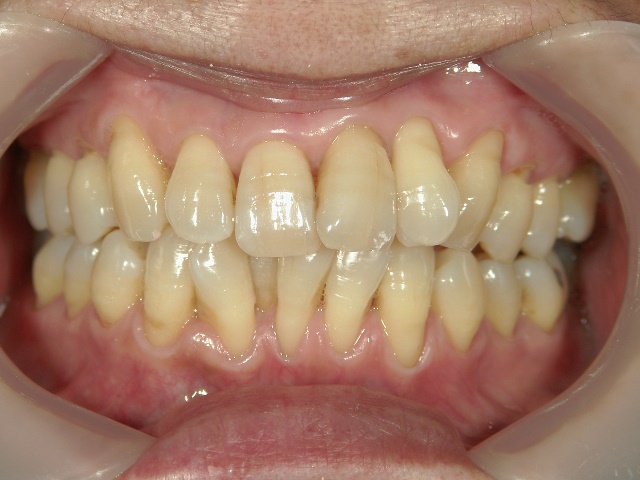

矯正歯科 治療後矯正歯科 プチワイヤー矯正 治療後矯正歯科(プチワイヤー矯正)治療後

矯正歯科 治療後

no.12_5333_治療後_左.jpgno.12_5333_治療後_正面.jpgno.12_5333_治療後_右.jpg